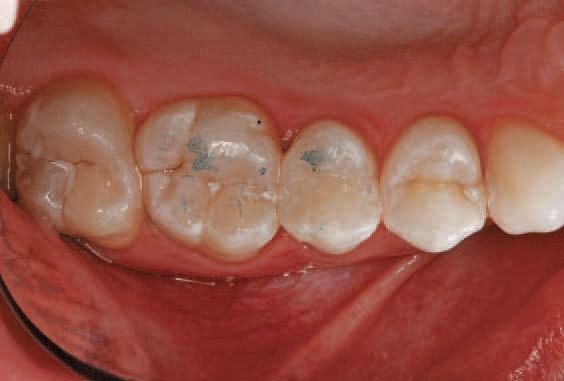

A 23-year-old female presented with caries on tooth No. 4 (Fig. 1 above). After the initial examination and consultation, the patient agreed to have the cavity filled with direct composite. The clinician recommended this nanohybrid composite to streamline the restorative procedure and provide a predictable and esthetic result.7-11

Occlusion and articulation were verified using articulation paper (Fig. 10).